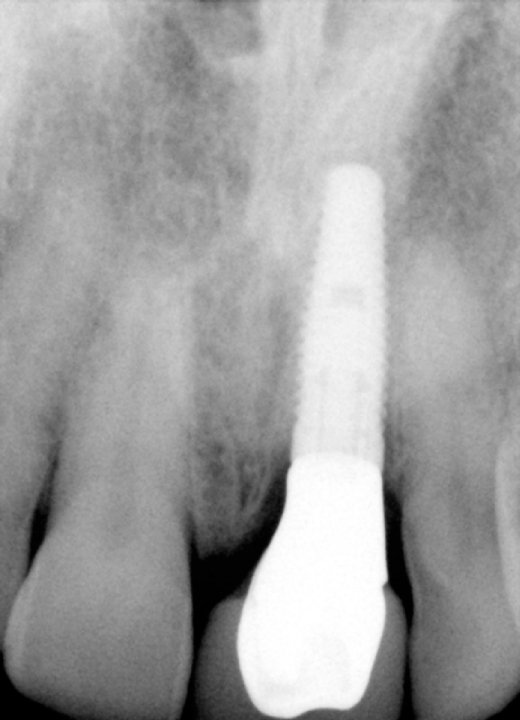

Final X-Ray Showing Implant

X-Ray Showing The Custom Abutment In Place